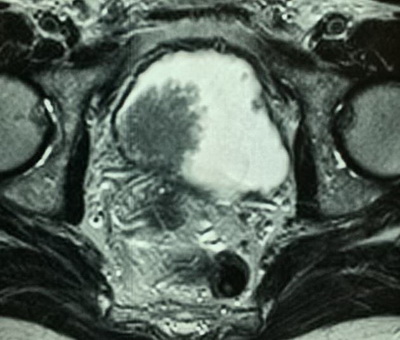

Диагноз: Рак мочевого пузыря T2bNoMo. Кисты правой почки.

Очередной эпизод макрогематурии отметил в начале декабря текущего года. Консультирован в клинике урологии УКБ№2 Первого МГМУ им. И.М.Сеченова, при обследовании (УЗИ, МРТ и МСКТ) диагностировано до 20 объемных образований мочевого пузыря. Госпитализирован в плановом порядке для обследования и лечения.